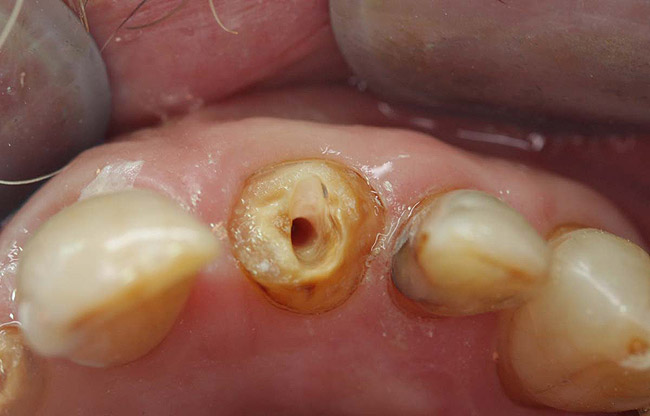

Figure 6  Endodontically treated maxillary right second molar.

Figure 6